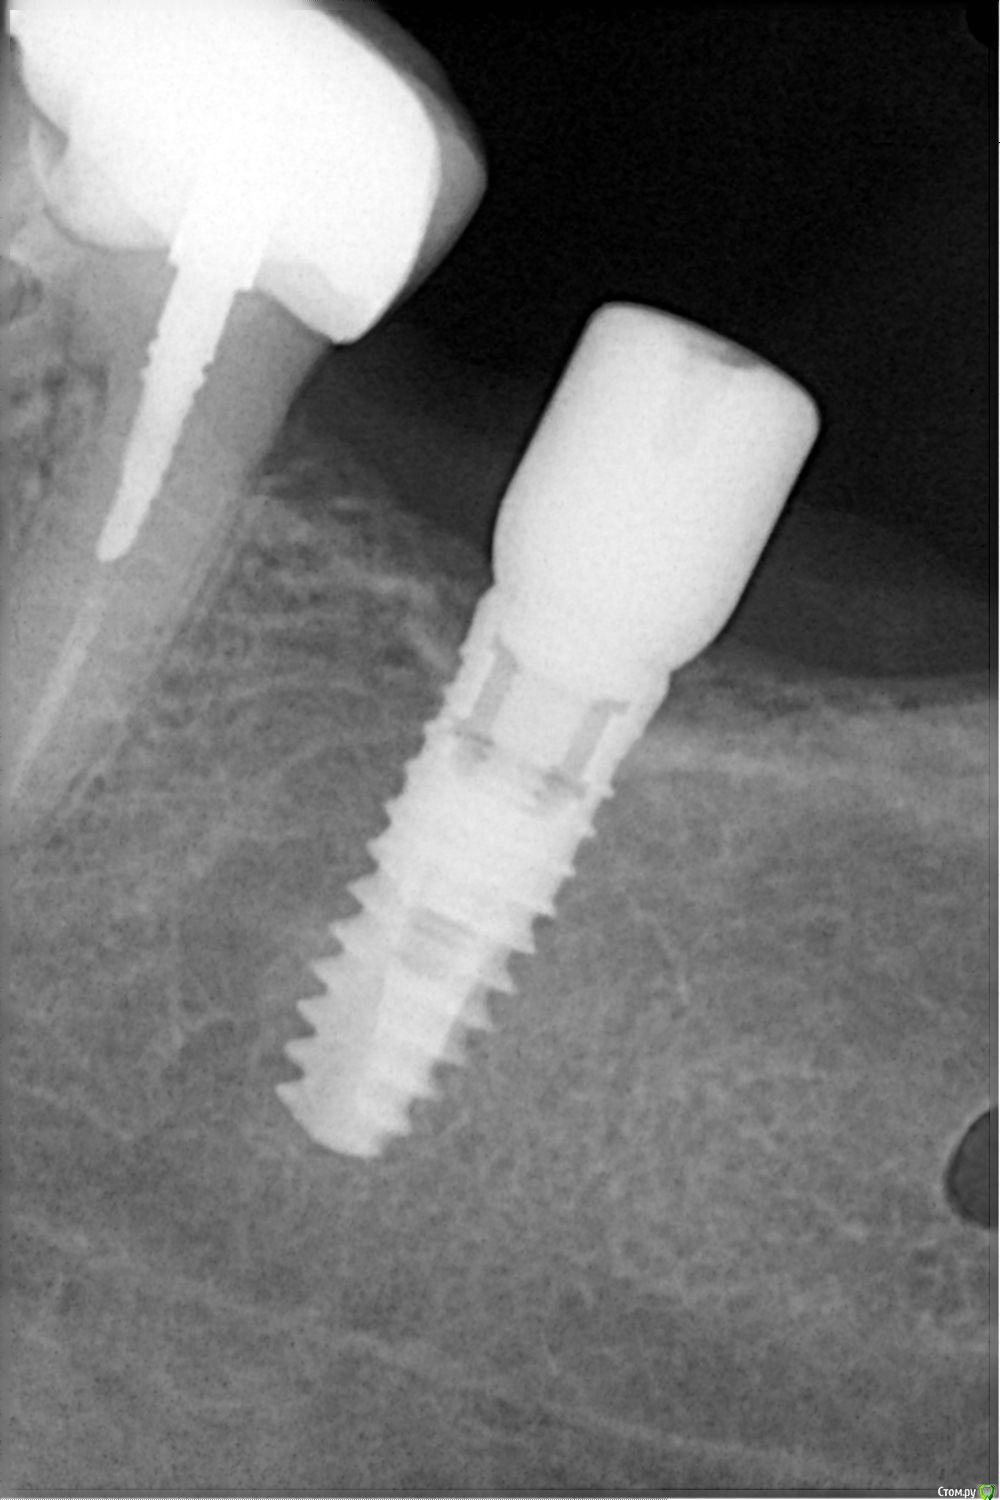

Sampson Опубликовано 8 сентября, 2018 Поделиться Опубликовано 8 сентября, 2018 Коллеги помогите опознать зверя.Пациентка обратилась с жалобой на выпадение фдм.С ее слов имплант установлен более 7 лет назад. Ссылка на комментарий

АнтонТЛТ Опубликовано 8 сентября, 2018 Поделиться Опубликовано 8 сентября, 2018 Похож на xive 4 Ссылка на комментарий

Sampson Опубликовано 8 сентября, 2018 Автор Поделиться Опубликовано 8 сентября, 2018 Похож на xive Спасибо!! Ссылка на комментарий